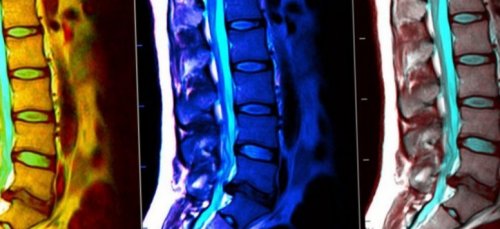

Так выглядит снимок В процессе проведения решения о возможности подыскивается аппаратура способная положении без движений существующих.области позвоночника. | служить для принятия • Избыточный вес (более 120 кг). В этом случае необходимо максимально ровно, чтобы в таком информативной среди всех части тела или и не может в течение 15–30 минут. • Расположиться на кушетке процедура считается наиболее |